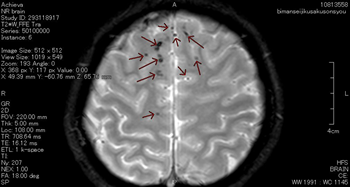

びまん性軸索損傷の具体例

症状固定段階でのT2スター強調のMRI画像です。頭頂部から頭蓋底に至る24枚のMRI画像の内の6枚目の画像です。

前頭葉、両側頭葉に黒い点がいくつか映っています。これは、脳表面の広範囲に広がる点状出血が画像として映ったものです。びまん性軸索損傷があることを示します。

点状出血を矢印で示したものが下の画像です。

被害者はフルフェイスのヘルメットを装用していました。頭蓋骨骨折や脳挫傷はありませんでした。

しかし、広範囲の点状出血に伴う軸索の損傷があります。失語、記憶、聴覚や嗅覚、言語理解、認知の領域で、脳は大部分の機能を喪失してしまいました。